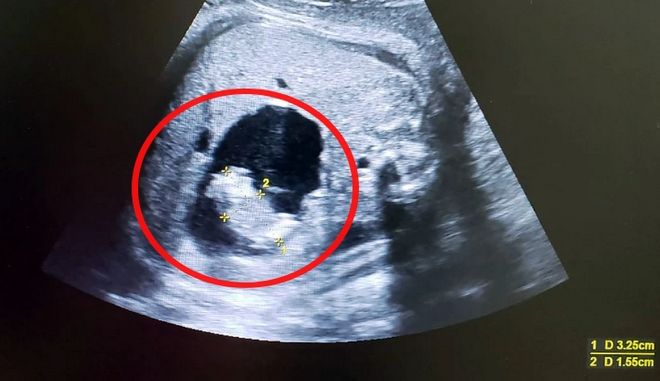

Χρησιμοποιώντας υπερηχογράφημα ο Δρ. Parra-Saavedra διαπίστωσε ότι η εν λόγω "κύστη" γεμάτη υγρό, περιείχε ένα μικροσκοπικό βρέφος, το οποίο μάλιστα υποστηριζόταν από ένα ξεχωριστό ομφάλιο λώρο που συνδεόταν με το έντερο του μεγαλύτερου βρέφους.

Στις 22 Φεβρουαρίου, και ενώ η μητέρα διένυσε την 37η εβδομάδα της εγκυμοσύνης της, οι γιατροί αποφάσισαν να προχωρήσουν σε καισαρική τομή, καθώς φοβόντουσαν ότι το εσωτερικό δίδυμο θα συνέθλιβε την κοιλιακή χώρα του εξωτερικου. Την επομένη της γέννας αφαίρεσαν το ύψους πέντε εκατοστών έμβρυο από τη κοιλιά του βρέφους με λαπαροσκοπική χειρουργική επέμβαση: Είχε αναπτύξει κεφάλι και άκρα αλλά στερούνταν εγκέφαλου και καρδιάς.